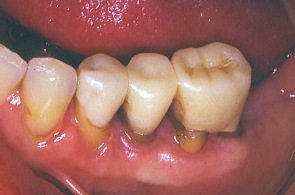

歯科医院指導の下、患者の熱心な歯磨きと衛生士の機械的清掃により、初診時に比べ歯ぐきが引き締まった。

最初の写真は先にワックスで作った形を模倣して口腔内で再現し、仮り歯を作ったもの。次の写真は歯周外科を施し、深い歯周ポケットの歯垢を除去したところ。歯肉の色や艶が健康色を取り戻した。